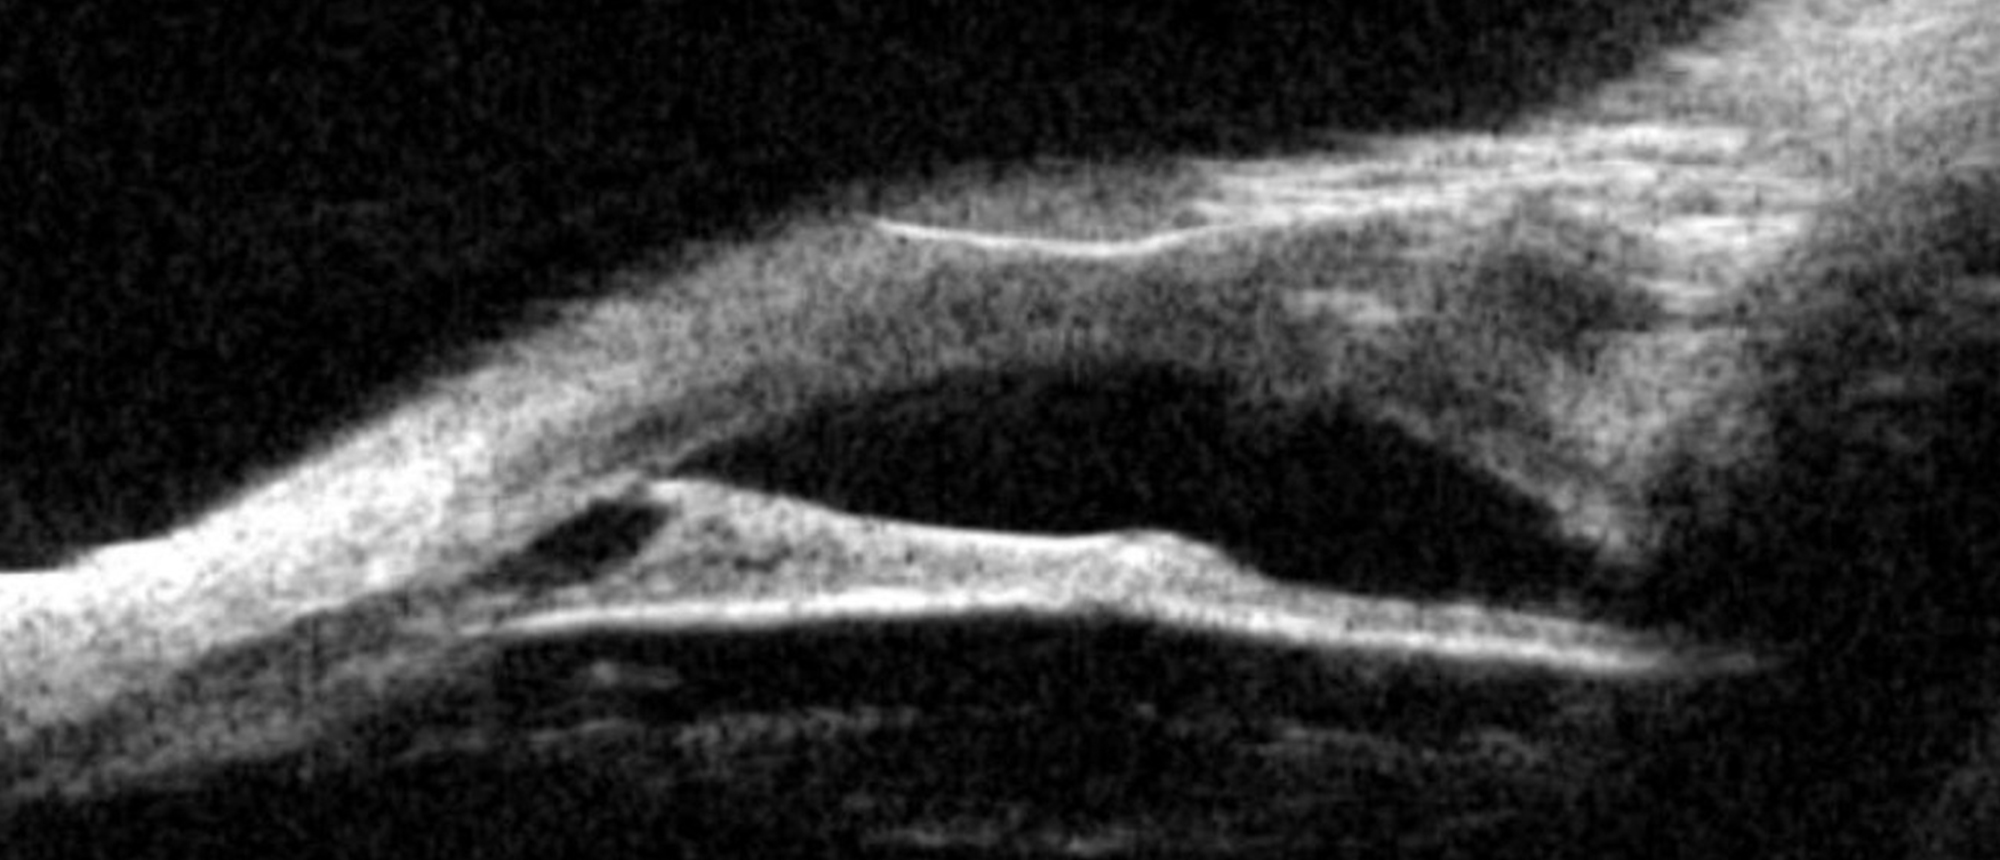

Retinal Tear An asymptomatic patient presented for routine ophthalmic examination. The anterior segment examination was significant for cataracts in both eyes. The dilated fundus examination revealed a superotemporal horseshoe tear (HST) with surrounding subretinal fluid in the right eye and was no…

A patient with double Torpedo Maculopathy lesions in the left eye. Two lesions are noted inferior to the macula with associated RPE changes and overlying fluid. Funds autofluorescence images show areas of hypofluorescence and hyperfluorescence correlating with the RPE changes on fundus photos.